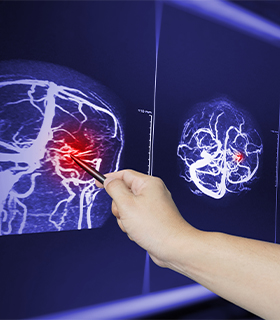

Aneurysm Clipping

Procedure to place a metal clip at the base of a brain aneurysm to prevent rupture and bleeding.

Arteriovenous Malformation (AVM) Surgery

Surgical removal or treatment of abnormal tangles of blood vessels in the brain to prevent bleeding and seizures.